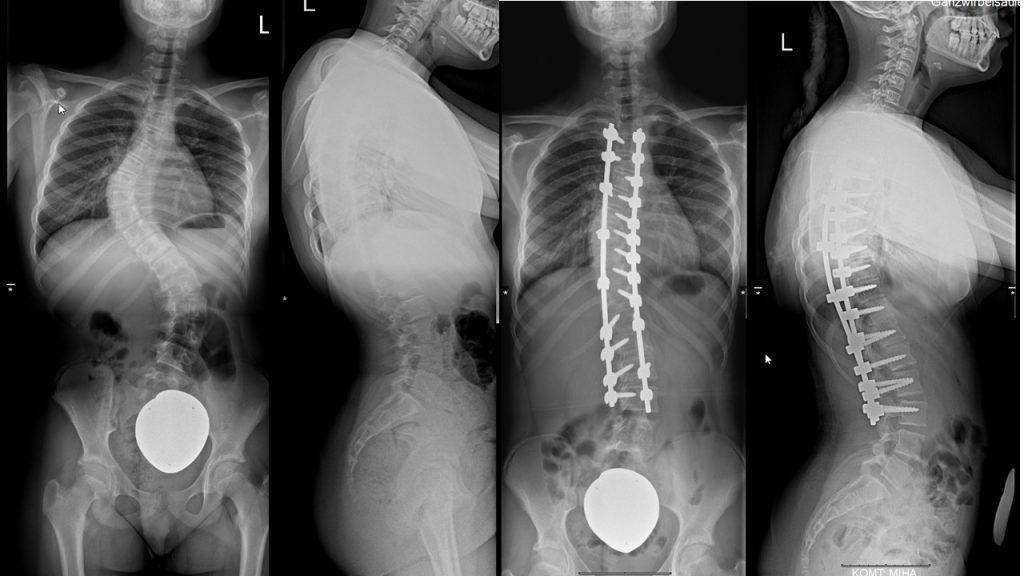

Skoliosetherapie (Chêneau-Korsett, operative Behandlung)

Das Chêneau-Korsett wird bei Patienten angewendet, die sich im Wachstumsalter befinden und an einer progredienten idiopathischen Skoliose leiden. Das Chêneau-Korsett ist asymmetrisch gebaut und bildet neben Druckzonen (Pelotten) auch Freiräume (Expansionszonen).

Beim Bau des Korsetts wird zunächst ein Gipsabdruck angefertigt. Daraus erstellt der Orthopädie-Mechaniker das Korsett mit drei Druckpunkten, um einen aktiven Ausgleich der Fehlhaltung zu erwirken. Wichtig ist eine gleichzeitige muskuläre Stabilisierung der Wirbelsäule, so dass wir unsere Patienten zu einer regelmäßigen sportlichen Betätigung ermutigen. Eine operative Korrektur ist nur bei einer geringen Zahl der Skoliosepatienten notwendig.